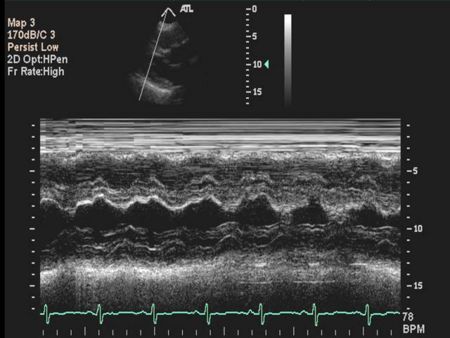

M mode echocardiography

A single crystal rapidly alternates between transmission and receiver modes with rapid updating result, rapidly moving structures (eg, valve leaflets) can be monitored for their characteristic motion very high temporal resolution

Ventricular M-mode